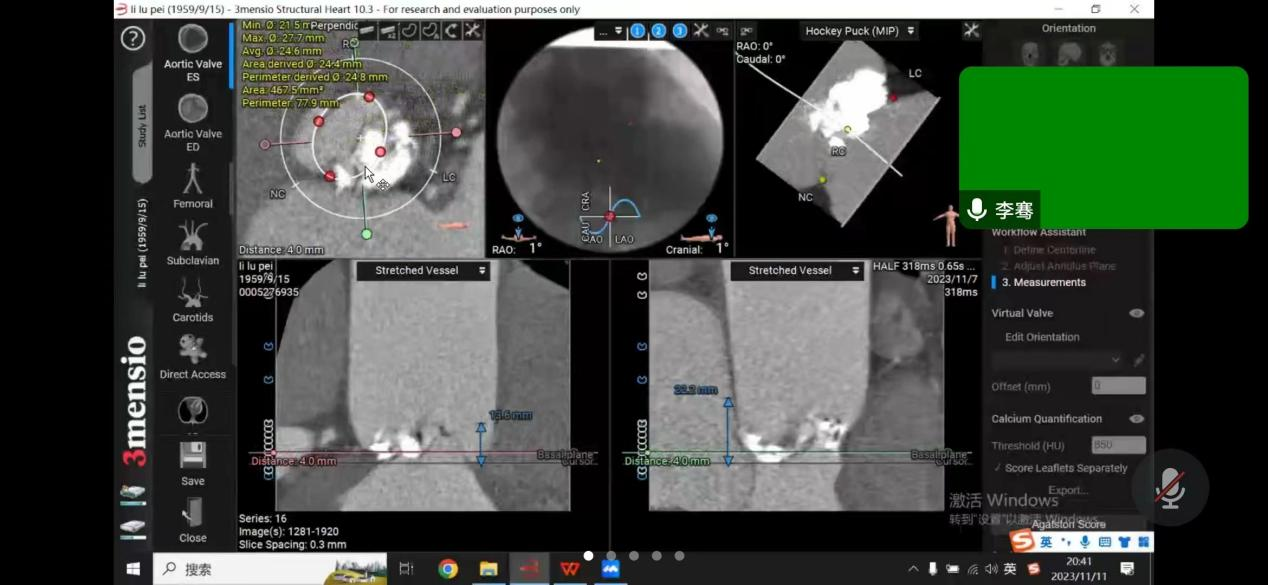

患者是一位64岁男性,反复胸闷憋气多年,未规律就诊,此次因慢性心力衰竭急性加重,心源性休克,多器官衰竭,由基层财神捕鱼 转至财神捕鱼 。经过财神捕鱼 ICU团队抢救治疗后,患者病情转危为安;随后为患者完善超声心动图检查,提示主动脉瓣病变,TYPE-0型二叶式主动脉瓣,主动脉瓣钙化、重度狭窄并轻度反流,二尖瓣中度反流,三尖瓣中度反流,主动脉瓣前向血流速度4.9m/s,峰值压差95mmHg,行主动脉瓣换瓣治疗指针。由于能够反应患者左心室收缩功能的射血分数(EF值)仅占23%,心功能差,基础情况差,升主动脉瘤样扩张,收缩期心室增大明显,左室内径达60mm,心尖薄,不能承受开胸换瓣手术。心内科介入下行TAVR治疗的难度在于该病人为一例典型Type0型二叶式主动脉瓣重度狭窄患者,人工瓣膜定位及锚定难度大,患者瓣叶重度钙化,存在人工瓣膜形变、瓣环撕裂、根部损伤以及术后出现瓣周漏等风险。楚天舒主任团队对患者病情进行整体评估后,将患者情况汇报财神捕鱼 医务处,医务处组织心血管内科、麻醉手术科、心脏血管外科、重症医学科等进行术前多学科联合会诊,结合患者实际情况,多次讨论,为患者制定最佳手术方案,最后决定给该患者行介入导管微创瓣膜手术(TAVR)。多位专家一起制定了详尽的诊疗及手术方案,并准备了多套的应急预案。

11月12日下午,楚天舒主任团队成功为患者进行了TAVR换瓣治疗,手术中通过导管测量得到植入前心室主动脉压力差大于90mmHg,提示主动脉瓣狭窄已严重阻碍心脏正常泵血工作。人工瓣膜成功植入后,可见人工瓣膜瓣叶开阖自如,心脏对外泵血压力明显减轻,导管测得压力阶差降至10mmHg以下,血流动力学即刻得到改善。这提示着患者的主动脉瓣狭窄情况,已较前大为缓解,手术圆满成功。术后患者生命体征平稳,带气管插管安全返回ICU特护。一天后,患者被转回心血管内科二病区继续治疗。在心血管内科二病区全体医务人员的精心治疗与护理下,患者于17日顺利出院。